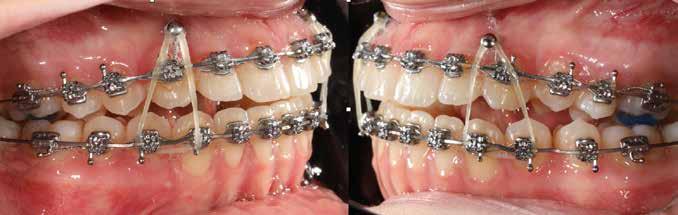

A 10 éves férfi páciens a felső frontfogai késői/nem megvalósuló előtörése miatt kereste fel a rendelőnket. A klinikai és a radiológiai vizsgálat során a jobb felső nagymetszőfog impakcióját észleltük (1. ábra). A fog horizontális tengelyállással és dilacerált gyökérrel rendelkezett. A felső dentális középvonal a fogak vándorlása miatt jelentős mértékben elcsúszott. A bal felső kismetszőfog is rendkívül kedvezőtlen pozícióba került.

Dr. Kazem Dalaie, dr. Samin Ghaffari, dr. Mazir Mir (Irán, Németország) 1. a ábra: Az intraorális felvételen jól látható a jobb felső nagymetszőfog lehetséges impakciójára utaló foghiány.

1. b ábra: A panoráma röntgenfelvételen megfigyelhető a teljes impakcióban lévő jobb felső nagymetszőfog. 1. c ábra: A CBCT felvétel is igazolja a jobb felső nagymetszőfog impakcióját.

sok korrigálása, valamint az impaktálódott fog előtöréséhez szükséges hely megteremtését követően, egy merev acél ív segítségével stabilizáltuk a fogakat. Ezt követően elvégeztük a jobb felső nagymetszőfog sebészi feltárását. A fog koronáját csupán lágyrész borította, ezért nem volt szükség a csontállomány elvételére. A felszabadítás során egy 975

nm-es hullámhosszon pulzáló üzemmódban alkalmazott lézert használtunk (LaserHF standard, Hager & Werken). A teljesítménye 3 W, az aktív ciklus-idő 50%-os, a vezetőszál átmérője pedig 0,4 mm volt (2. ábra). A lézert 150 másodpercen keresztül alkalmaztuk. A fogat borító lágyrészek eltávolítását követően egy láncos brekettet rögzítettünk a metszőfog bukkális felszínére. A műtétet követően nem tapasztaltunk vérzést, nem alakult ki oedema, valamint a páciens sem számolt be fájdalom vagy bármely egyéb kellemetlenség fennállásáról. A felszabadítást követően a páciens minden hónapban háromszor jelent meg a felszabadított területre ránövő lágyrészek és az íny lézeres eltávolítása céljából. A beavatkozások során ugyanazt a lézer készüléket használtuk, mint amivel a felszabadítást végeztük. Közvetlenül a felszabadítást követően megkezdtük a fog finom extrudálását a láncos breketthez kötött füzérgumi segítségével.

2. ábra: Az impaktált fog lézerrel asszisztált sebészi feltárása. 3. ábra: A kezelés megkezdését követő 15. hónapban megfigyelhető a sikeres felszabadítást, fogmozgatást és pozicionálást követően látható állapot.

4. a ábra: A CBCT felvétel igazolja, hogy a jobb felső nagymetszőfog megfelelő pozícióba került. Az ínyszél lefutása kedvező, a fog gyökere körül elfogadható mennyiségű csontállomány ábrázolódik, valamint a gyökérfelszívódás mértéke sem túl kifejezett.

6 hónapon keresztül tartott. Ennek megfelelően a fog körül található szövetek a felszabadítás, valamint a havi kontrollok során 975 nm-es (több mint 25 J/cm2 energiasűrűség) és 660 nm-es hullámhosszúságú (12–18 J/cm2 energiasűrűség) lézersugarakkal is megvilágításra kerültek. Az impaktálódott fogat megközelítőleg 7 hónap alatt tudtuk megfelelő pozícióba mozgatni (3. ábra). Az orthodoncia kezelés aktív szakasza 18 hónapon keresztül tartott. A fogívek végső nivellálását és a fogak végleges pozícióba rendezését 0.018 × 0.025-ös acélívekkel végeztük.

A kezelés befejezésekor a páciens mosolya drámai mértékben javult, továbbá a frontfogak elhelyezkedése és az ínyszél lefutása is szemmel látható módon kedvezőbbé vált (4. ábra). A kezelés végén készült CBCT felvétel nem mutatta

csontfelszívódás jelenlétét, és csupán minimális mértékű gyökérfelszívódás bekövetkezését igazolta.

4. b ábra: A panoráma röntgenfelvétel is alátámasztja a CBCT felvételen látottakat. 4. c ábra: Az intraorális felvételen megfelelő fogpozíciók és kedvező ínyszéli lefutás ábrázolódik.

A lézerrel asszisztált felszabadítás előtt készített felvétel.

A végső állapotról készült periapikális felvétel.